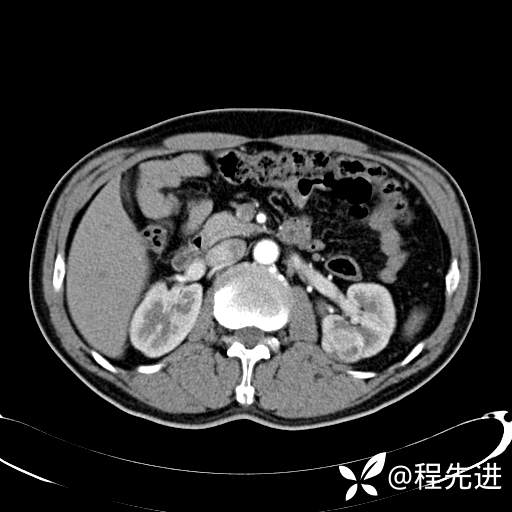

患者性别:男

患者年龄:65岁

简要病史:腰痛2月,体检发现左肾占位5天

髓质期: